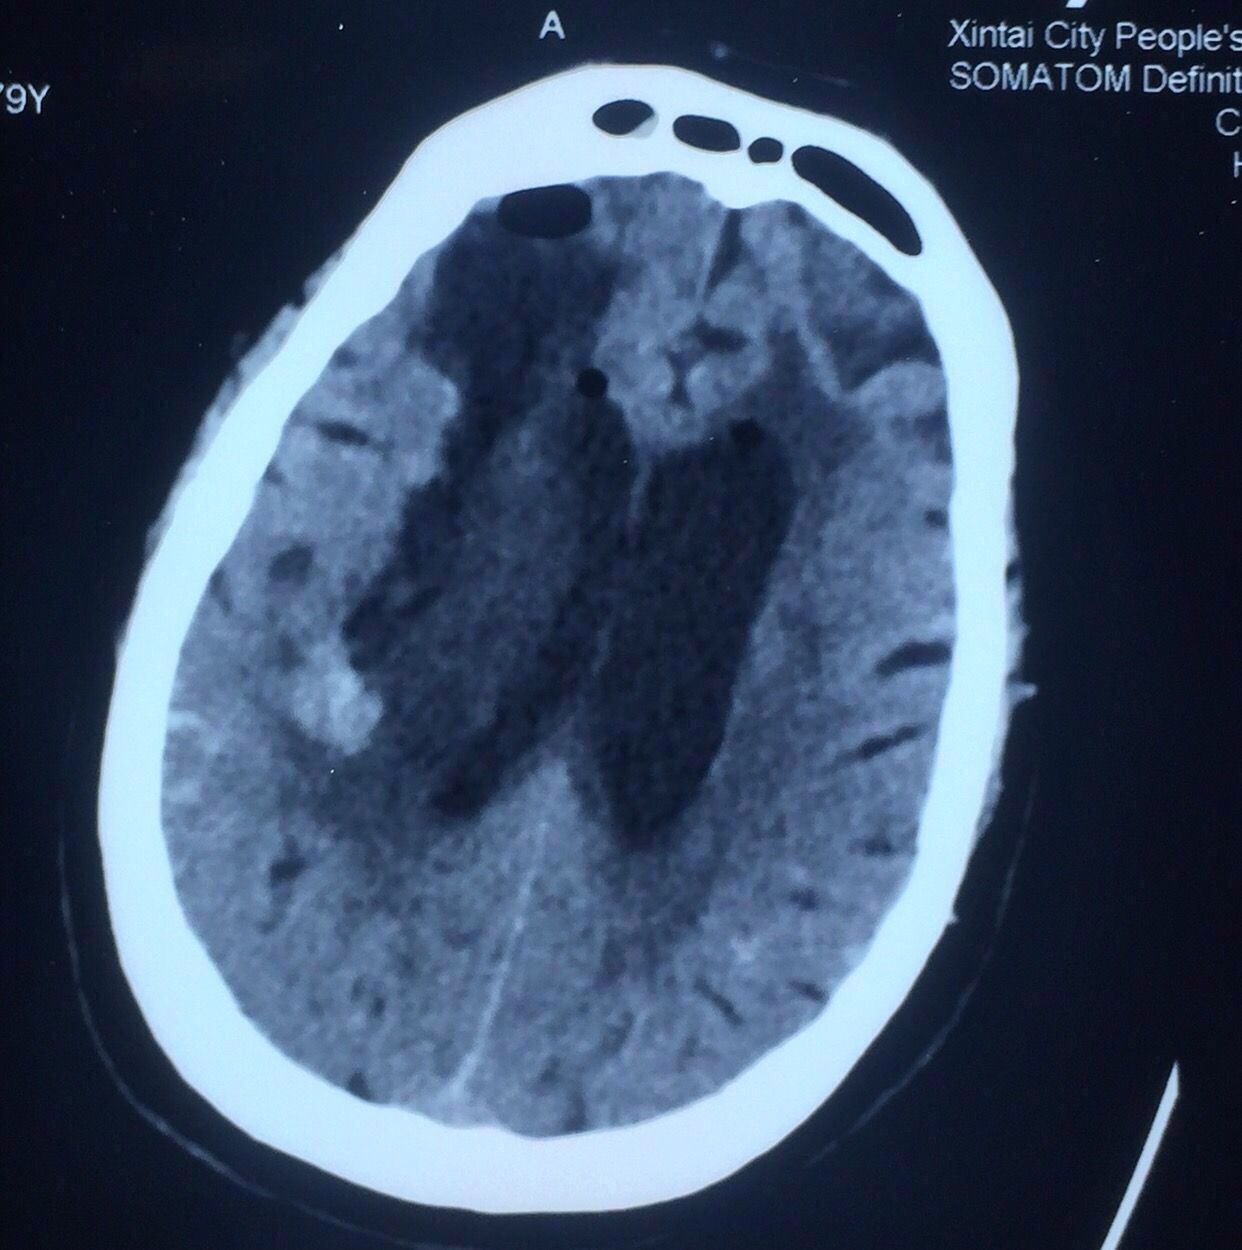

次日复查如上图:

出血未再增大。

病人仍昏迷状态,已气管插管,血氧差,呼吸机辅助呼吸。

入院3天后家属最终决定手术治疗。